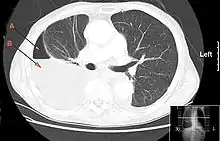

CT chest showing large right sided hydro-pneumothorax from pleural empyema. Arrows A: air, B: fluid